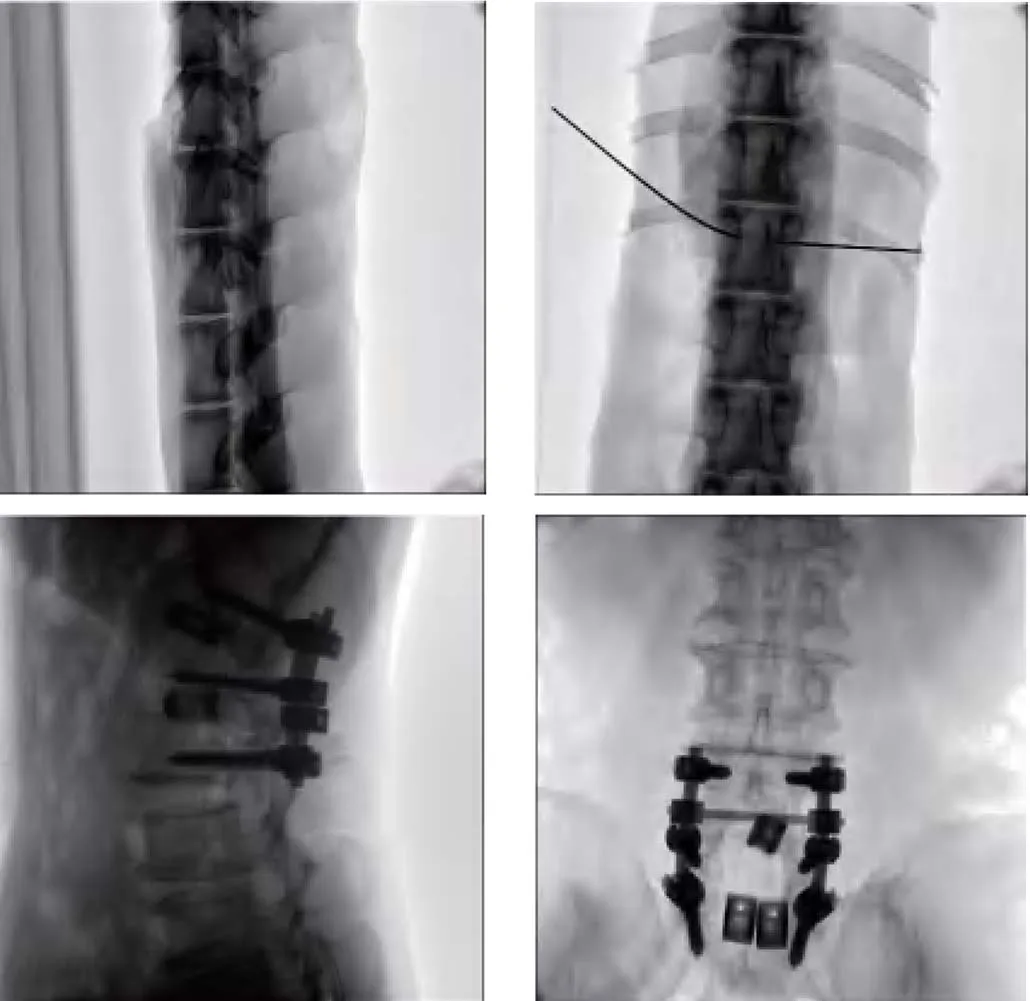

The workstation system has eight pre-selected modes (abdomen, vertebra, hips, limbs, etc.) for automatic dose fluoroscopy. |

Metal artifact removal technology to remove artifacts caused by metals such as metal nails or metal stents. |